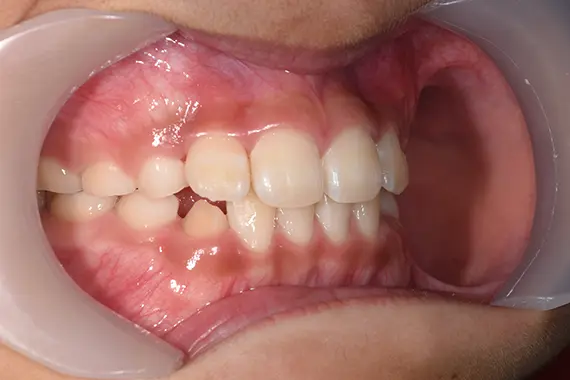

矯正後:横から

| 治療名 | ムーシールド使用の一期治療(就学前の一期治療) |

| 治療回数・期間 | 約3年(ムーシールド2年・一期治療1年) |

| 治療費(税込) | 385,000円 |

「受け口」への対処を早期の内に行うと、「上あごの成長阻害」という重大な弊害を回避することが出来ます。 「受け口」の治療は長期間になりますし、経過観察もしっかりと診てゆく必要がある治療です。 |